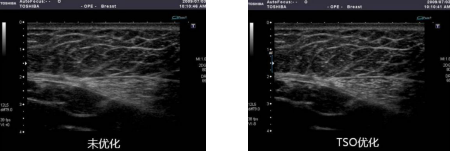

u 组织特异性优化成像TSO(Tissue Specific Optimization)

传统超声设备在成像时假定声速是恒定的,这样的假定难以反映人体不同组织中声速的变化,特别是在对一些肥胖病人检查时,由于超声波在脂肪层与在肝脏、乳腺实质内传播的速度存在有较大差异,如若对此未加校正,采用固定的声速值计算成像将造成接收的回波信号失真,从而带来不真实的图像再现,影响医生做出正确诊断。TSO 组织特异性优化技术可以对在脂肪组织中较低的传播声速予以补偿,纠正误差,带来图像的真实再现,提高图像的细微分辨率。该技术具有多级调节,满足不同程度的肥胖患者乳腺、腹部脏器检查需要。